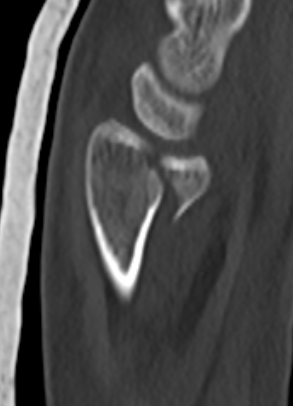

![]() |